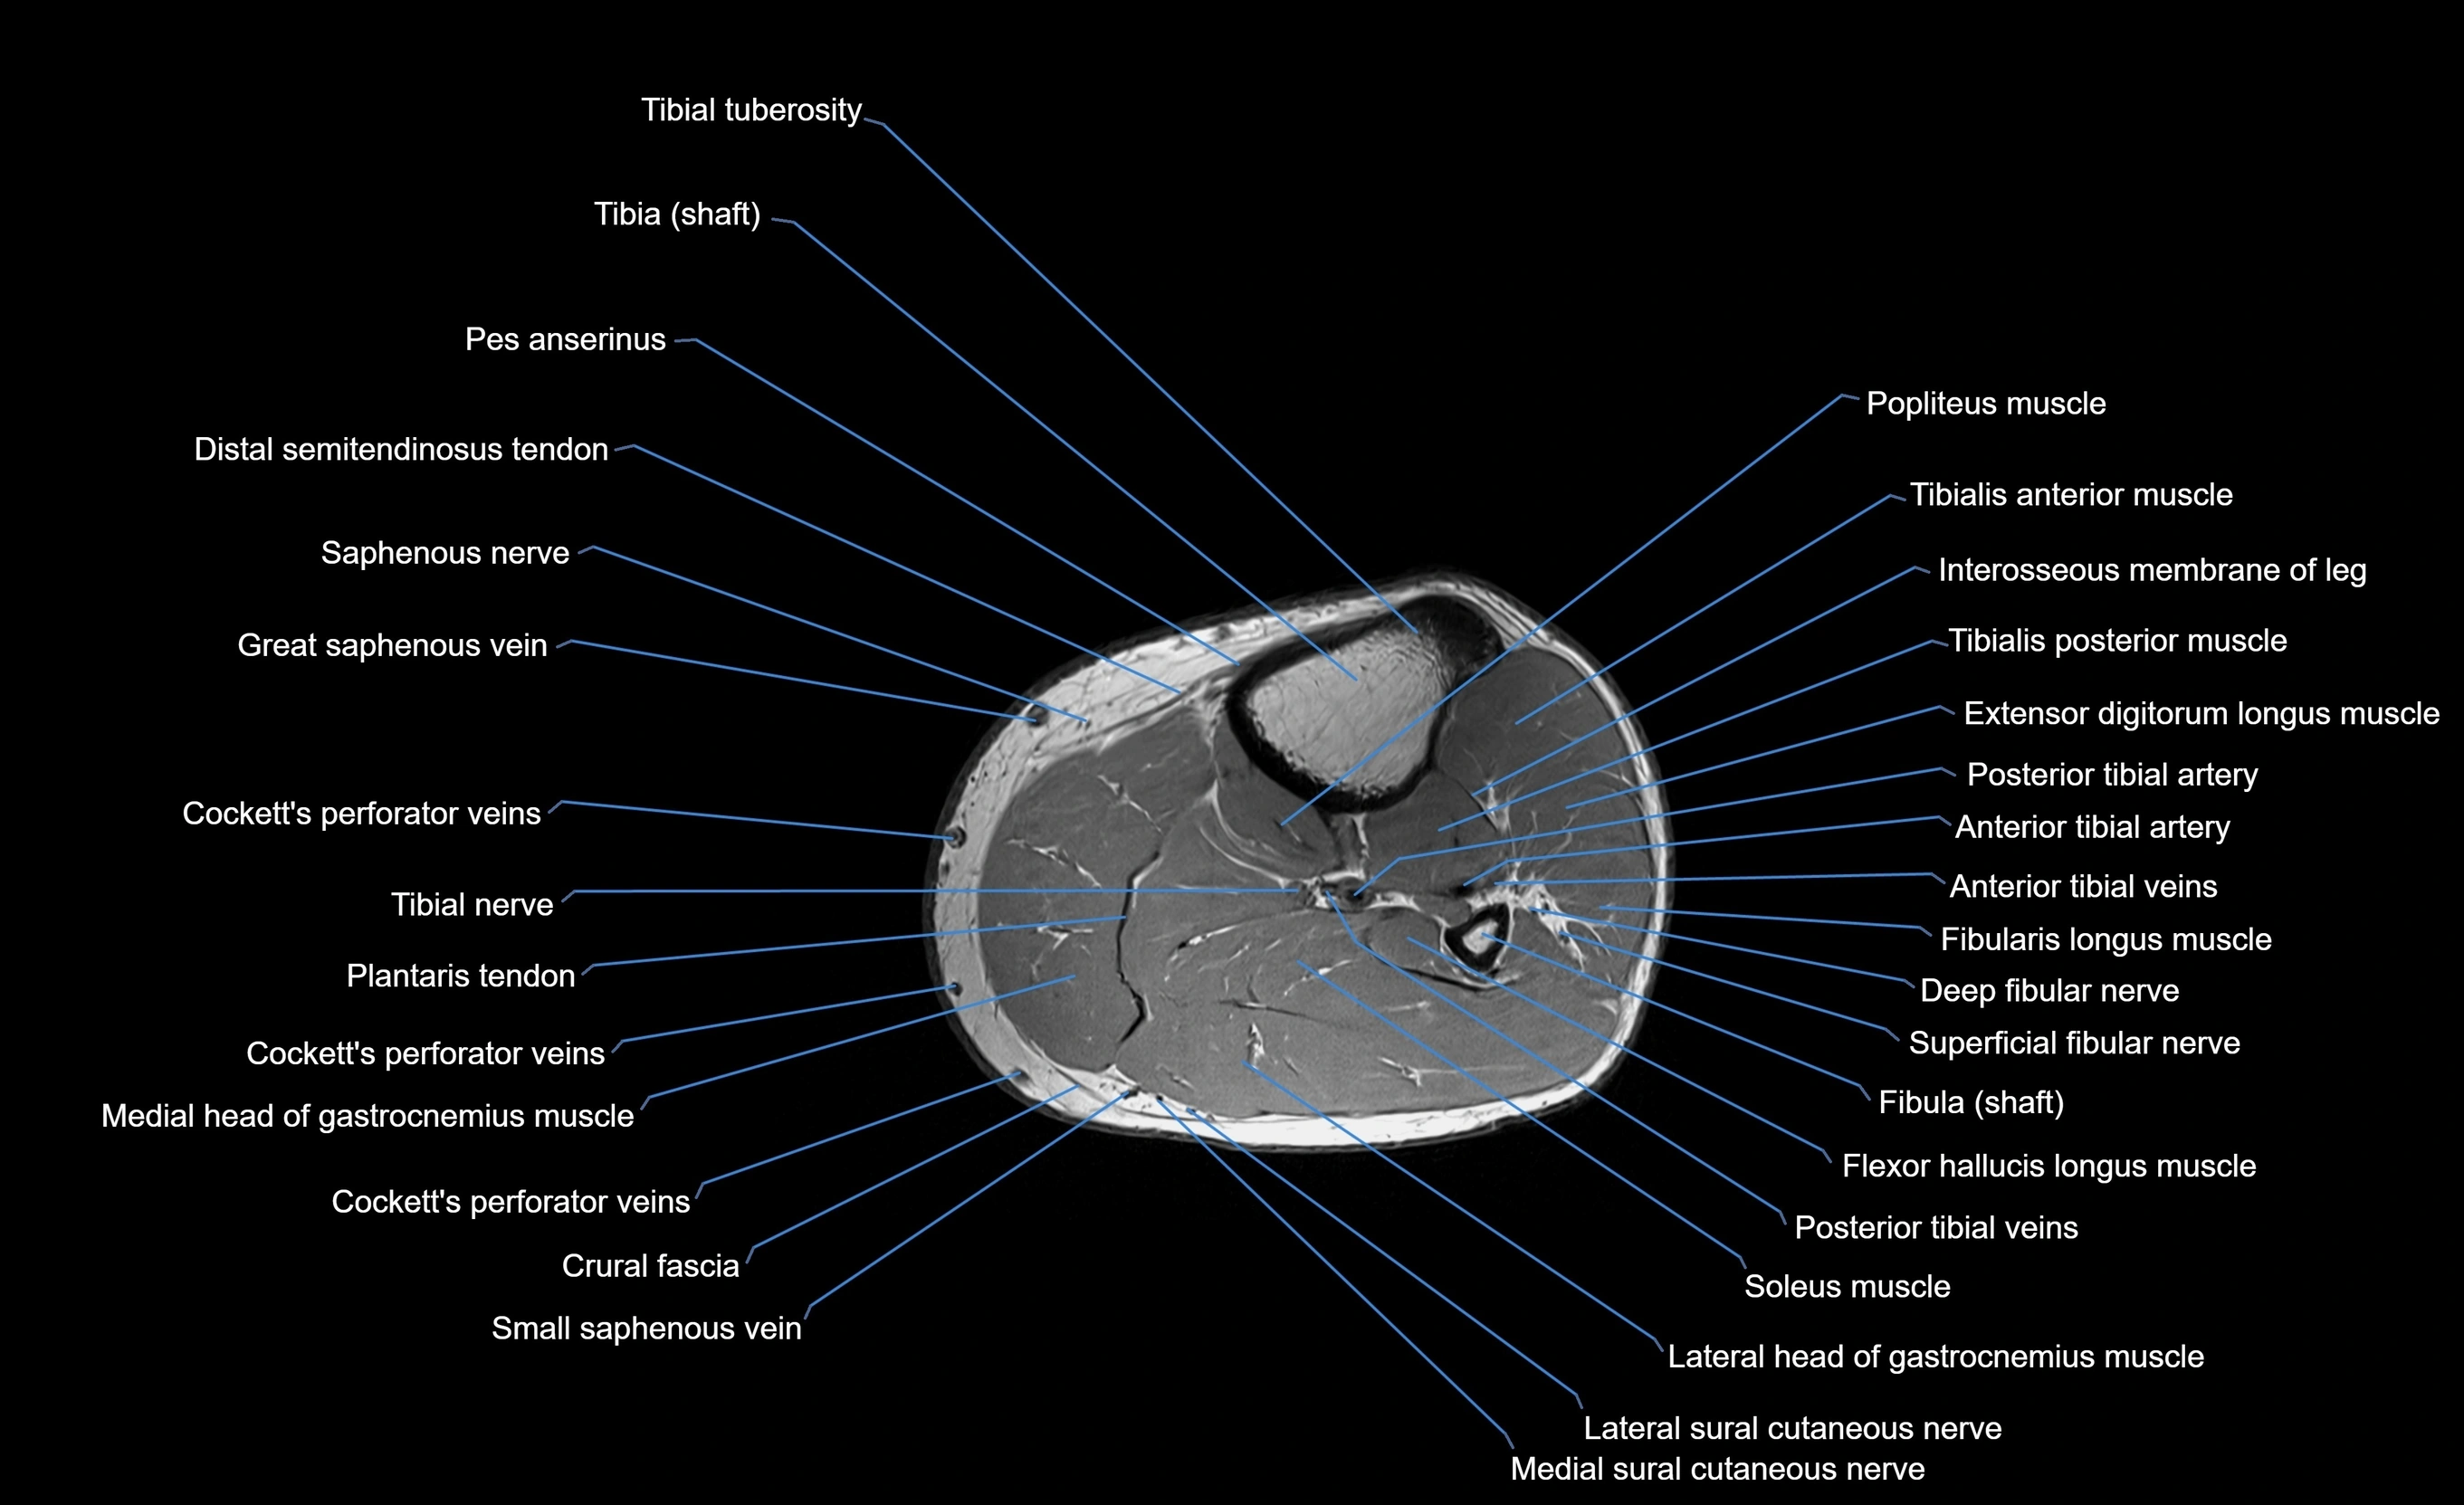

MRI image